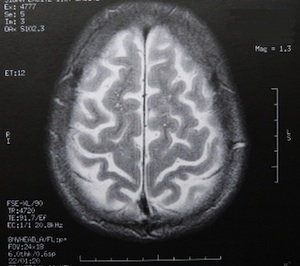

Sie sind hier: Startseite Berichte Wissenschaft fMRI-Studie bestätigt letztendlich, dass Gehirngewebe auf Licht reagiert Bild: pixelio.de/Dieter Schütz